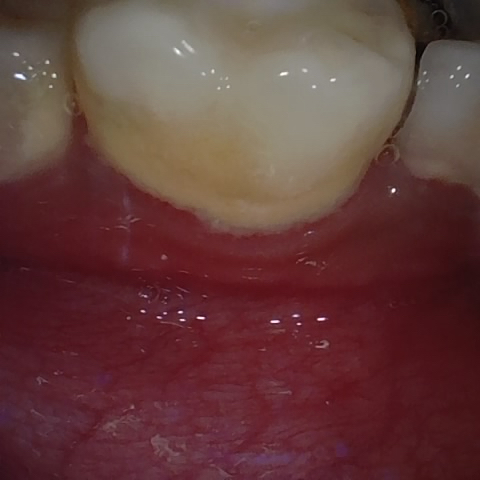

Annotated as "Good"